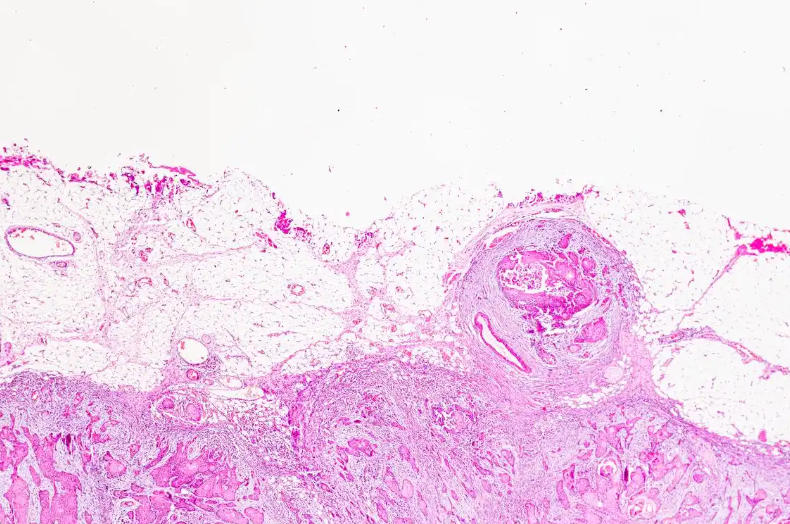

Animal slices also play an important role in new drug development and disease treatment. Researchers can assess the safety and efficacy of drugs and screen for potential therapeutic agents by observing their effects on specific cell types. Furthermore, animal slides can be used to study the pathogenesis and pathological changes of diseases, providing a reference for developing effective treatment plans.